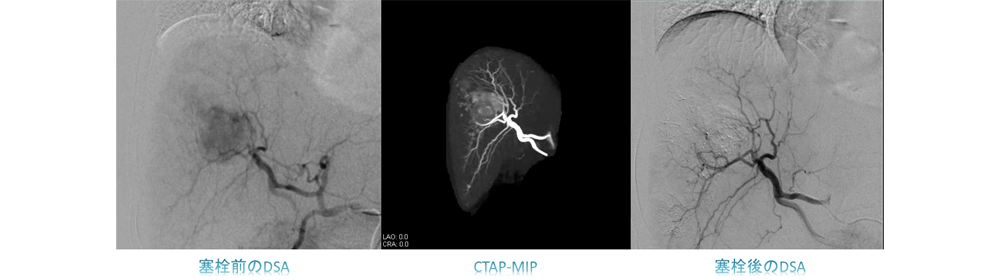

頭頚部・脳血管撮影検査・治療

脳血管に直接カテーテルを挿入し、詳細な脳血管の血流や走行、形態情報を得るために行う検査です。脳動脈瘤や脳血管および脊椎動脈における動静脈奇形などの診断カテーテル検査をはじめ、動脈瘤に対するコイル塞栓術、頸動脈狭窄に対するステント留置術(CAS:Carotid Artery Stenting)、脳腫瘍に対する開頭手術前の腫瘍塞栓術、硬膜動静脈瘻などのシャント性疾患に対する塞栓術など様々な疾患に対する治療も行っています。

当院で使用している装置はFPD搭載のバイプレーン血管撮影装置であり、循環器領域をはじめ、20inchの大型パネルで全身に対応できる装置であり、特に脳血管内治療を強力にサポートする豊富なアプリケーションが導入されています。Pixel size 154μm、濃度分解能16bitの性能を持つFPDは、高精細な3Dイメージングや、頭蓋内の穿通枝レベルの微細な血管や周辺解剖、およびデバイスの描出に優れた性能を有し、画質を維持しながら最大73%被ばくを低減し、患者様に、精度高く安全に配慮した検査・治療を受けていただける装置として位置づけられています。